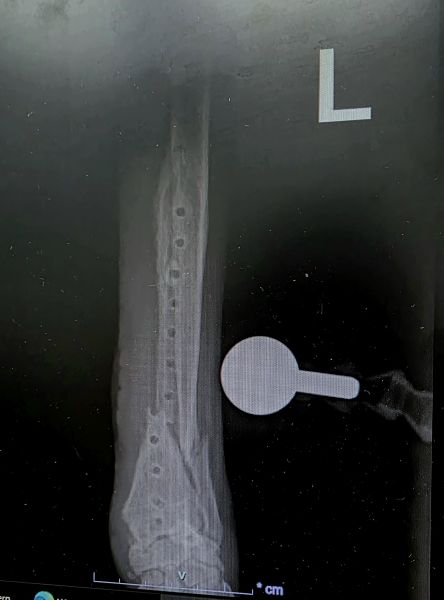

My 5-year-old Canaan dog (43 kg) had a distal radius-ulna fracture in his left front leg about three years ago, treated with a titanium plate and 12 locking screws. Since the surgery, he remained mildly lame but otherwise active and functioning well.

Recently, the lameness worsened - he began avoiding the leg completely. A CT scan indicated reasons to remove the implant, and a week and a half ago we went ahead with the removal surgery. He showed improvement over the next two days, but on day three, after suddenly jumping up in fear, he stopped using the leg again. An X-ray revealed a new fracture near the previous fixation site.

Attaching: CT before implant removal + Radiograph post-removal showing the new fracture.